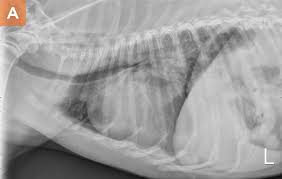

Common Respiratory Problems In Dogs Aesc Parker

Common Respiratory Problems In Dogs Aesc Parker from aescparker.com

Bacterial pneumonia is an inflammation of the lung usually caused by bacterial or viral infection but can be caused by inhalation of an irritant. Some of the symptoms may include: These are far, far more common causes of your dog's coughing, shortness of breath, or difficulty in breathing than lung cancer. Since lung cancer affects the respiratory system in our furry friends, most of the symptoms of this disease will reflect that. The infection that causes pneumonia will often cause a high fever in dogs. However, there are some other symptoms that lung cancer can cause in dogs if the disease has spread to other parts of the body. It is important to look for pneumonia in patients that may have been vomiting, have undergone anesthesia, prolonged recumbency, have megaesophagus, immune compromise or airway susceptibility (e.g. Pneumonia is a diagnosis that will commonly be made in dogs with a cough or hacking, with or without evidence of a fever.

Pneumonia is an infection of lung tissue usually caused by viruses, bacteria, fungi, and/or parasites.however, bacteria and viruses cause the majority of pneumonia infections.